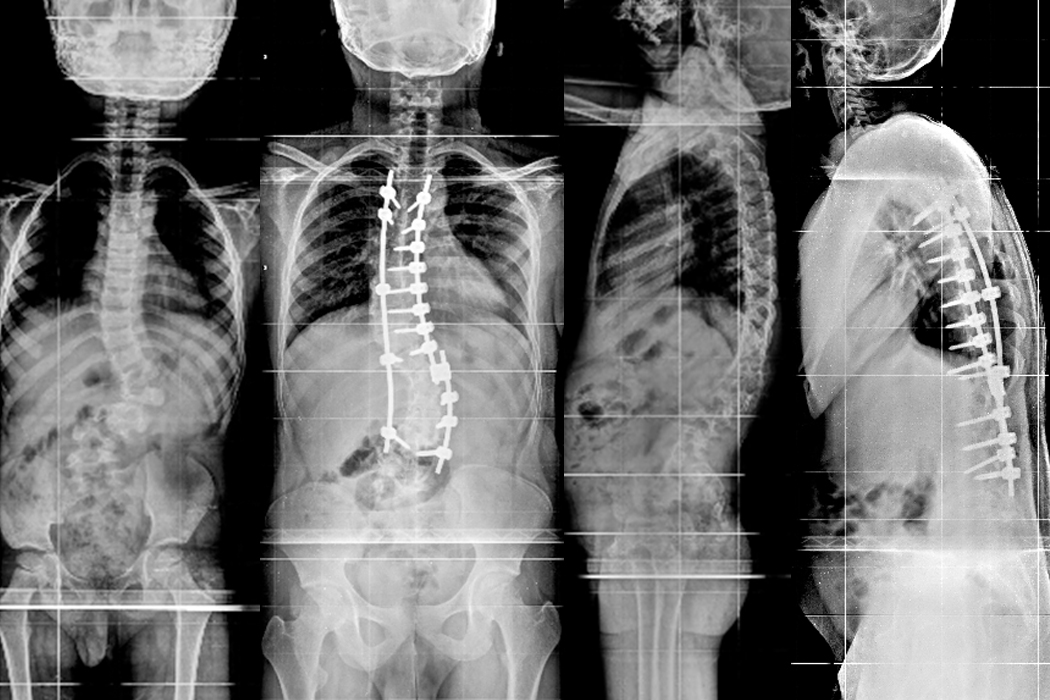

Patient E

An 8 year old child presented with deformity of back (scoliosis) in 2013. Then he was applied Growing Rod construct and was under regular follow up. In every 6 months distraction of Growing Rods were done for the last 8 years. Finally surgery of Posterior scoliosis correction and fusion was done on 20.08.2021.